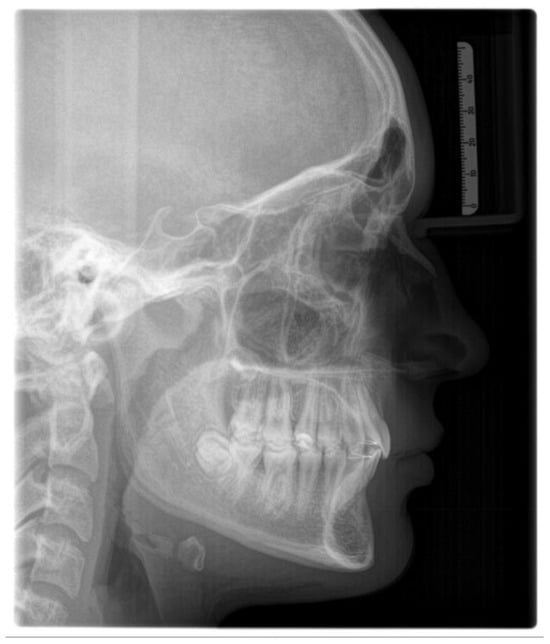

3.3.1. Lateral Cephalometric Radiography

- Sella (S)—the center of the hypophyseal fossa (sella turcica).

- Nasion (N)—the junction of the nasal and frontal bones at the most posterior point on the curvature of the bridge of the nose.

- A-point (A)—an arbitrary measurement point on the innermost curvature from the maxillary anterior nasal spine to the crest of the maxillary alveolar process. A-point is the most anterior point of the maxillary apical base.

- B-point (B)—an arbitrary measurement point on the anterior bony curvature of the mandible. B point is the innermost curvature from the chin to the alveolar junction.

- Pogonion (Pg)—the most anterior point on the contour of the chin.

- Menton (Me)—the lowest point on the symphysis of the mandible.

- Gnathion (Gn)—the most outward and everted point on the profile curvature of the symphysis of the mandible, located midway between Pogonion and menton.

- Orbitale (Or)—a point midway between the lowest point on the inferior margin of the two orbits.

- Gonion (Go)—a point midway between the points representing the middle of the curvature at the left and right angles of the mandible.

- Porion (Po)—the midpoint of the upper contour of the external auditory canal (Anatomic Porion) or a point midway between the top of the image of the left and right ear-rods of the cephalostat (Machine Porion).

- Sella-Nasion (S-N)—a line connecting S to N;

- Frankfurt horizontal (FH)—a line connecting Po to Or;

- Mandibular plane (MP)—a line connecting Go to Me;

- Y-axis (Y)—a line connecting S to Gn;

- Upper anterior facial height (UAFH)—a line connecting N to ANS;

- Lower anterior facial height (LAFH)—a line connecting ANS to Me;

- Nasion-A point (N-A)—a line connecting N to A;

- Nasion-B point (N-B)—a line connecting N to B.